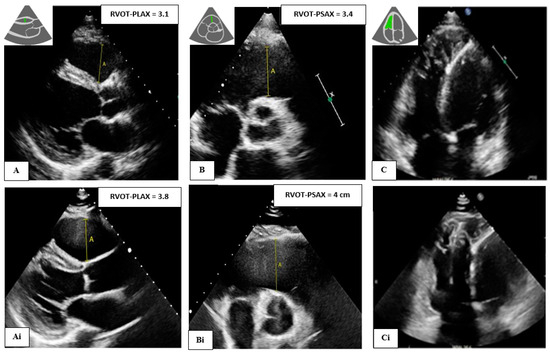

| Echo data | ||||

| RVOT-PLAX (cm) | 3.0 (2.5, 3.5) | 2.7 (2.4, 3.0) | 3.3 (2.7, 4.0) | <0.001 |

| RVOT-PSAX (cm) | 3.2 (2.9, 3.7) | 3.0 (2.7, 3.3) | 3.5 (3.0, 4.0) | <0.001 |